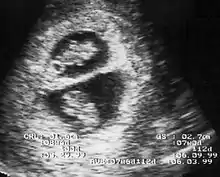

Diagnosis

By performing an obstetric ultrasound at a gestational age of 10–14 weeks, monochorionic-diamniotic twins are discerned from dichorionic twins. The presence of a "T-sign" at the inter-twin membrane-placental junction is indicative of monochorionic-diamniotic twins (that is, the junction between the inter-twin membrane and the external rim forms a right angle), whereas dichorionic twins present with a "lambda (λ) sign" (that is, the chorion forms a wedge-shaped protrusion into the inter-twin space, creating a rather curved junction).[4] The "lambda sign" is also called the "twin peak sign". At ultrasound at a gestational age of 16–20 weeks, the "lambda sign" is indicative of dichorionicity but its absence does not exclude it.[5]